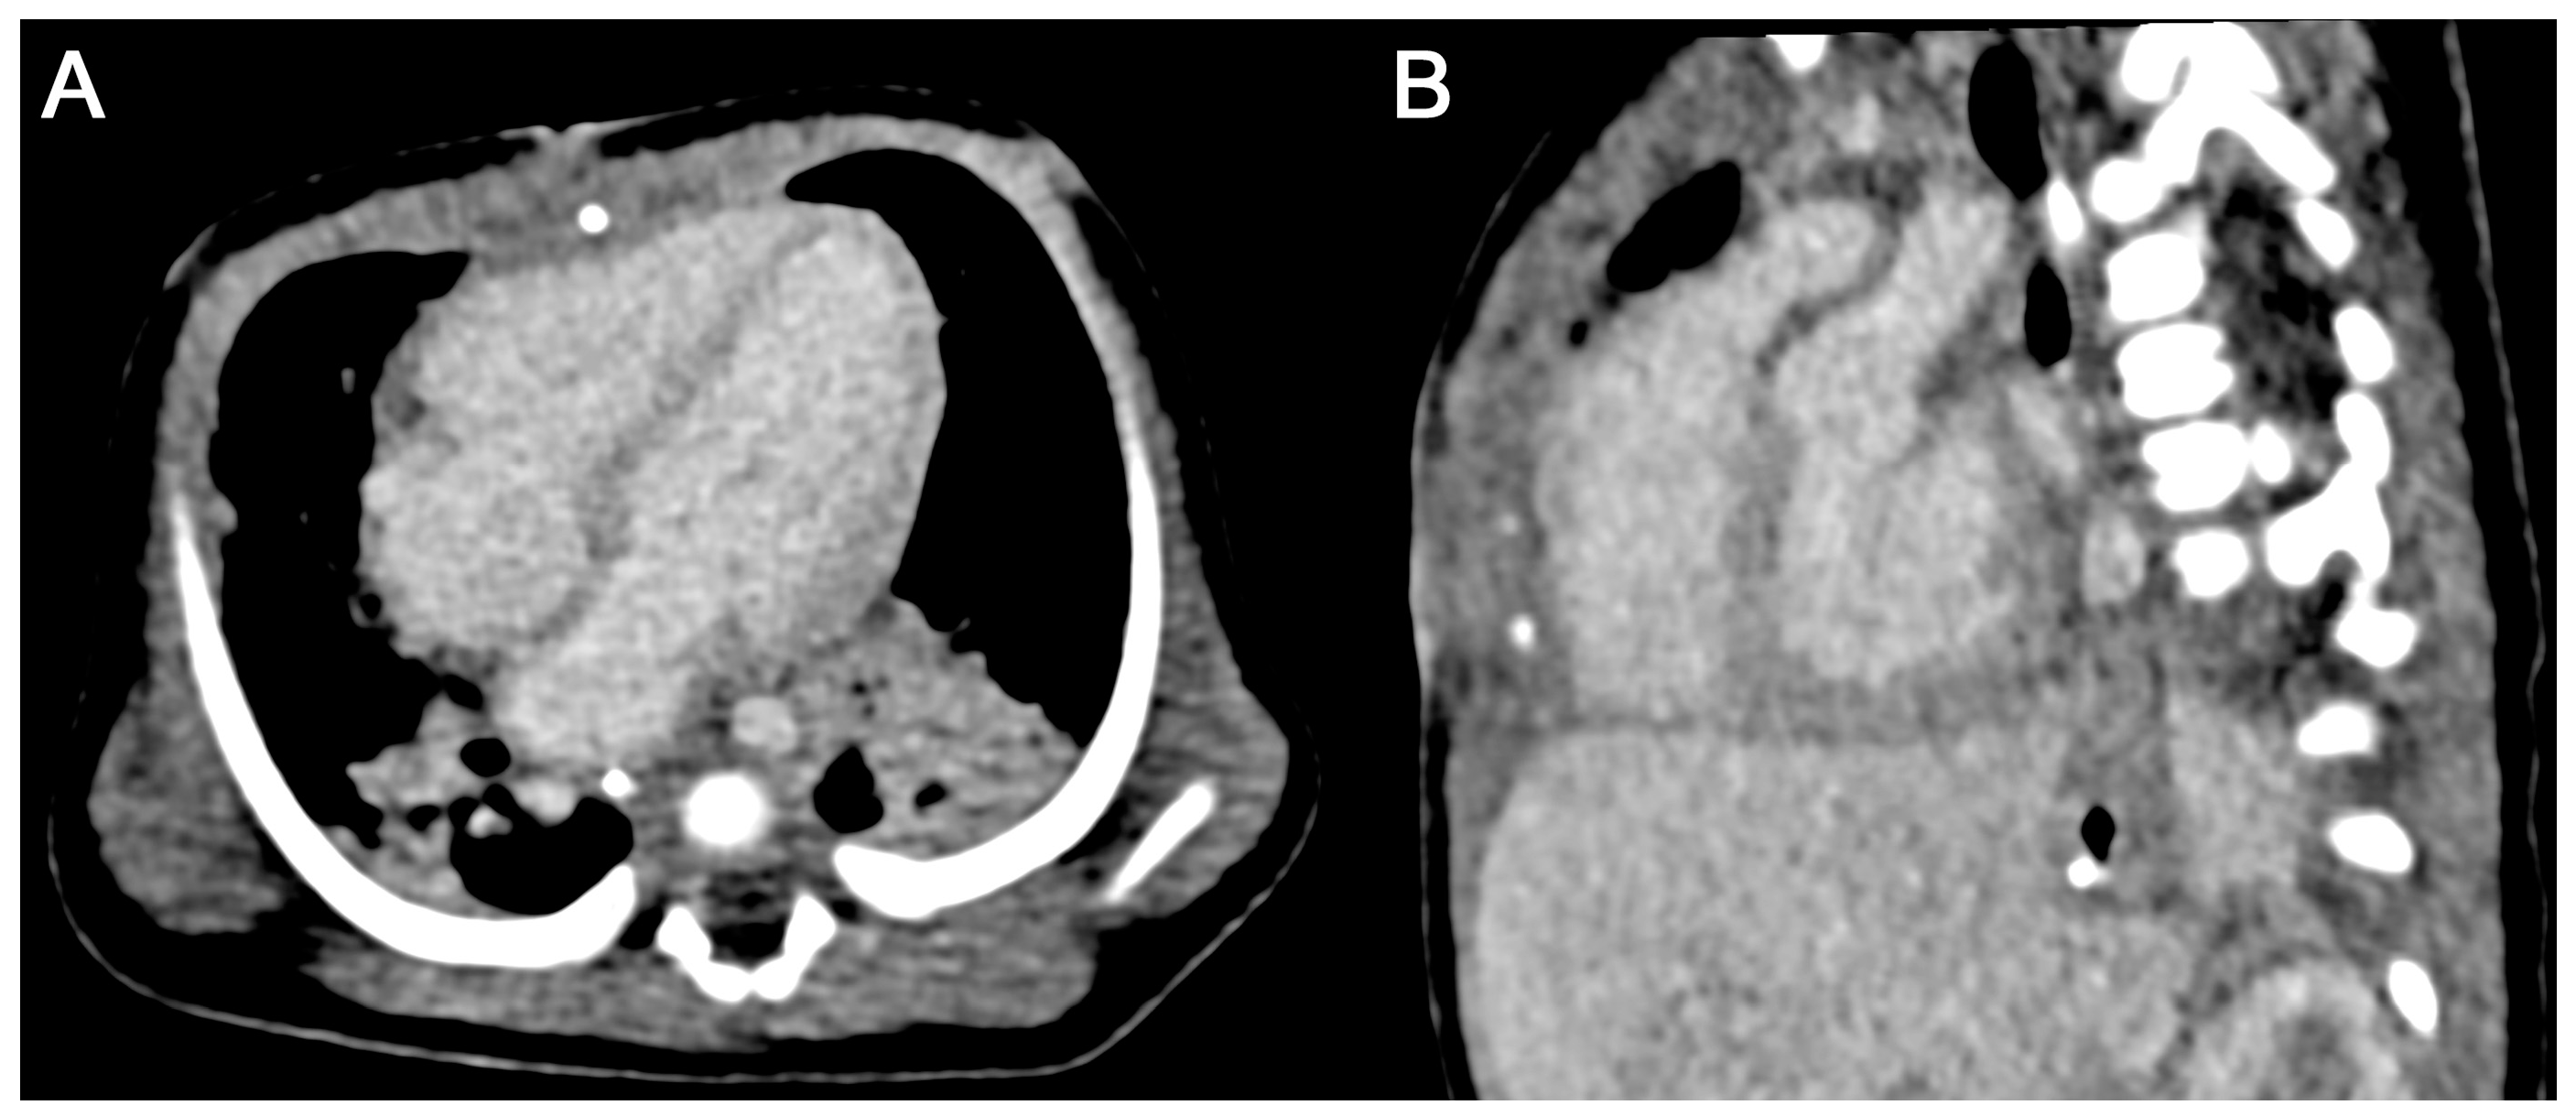

3.3.2. Subjective Image Quality